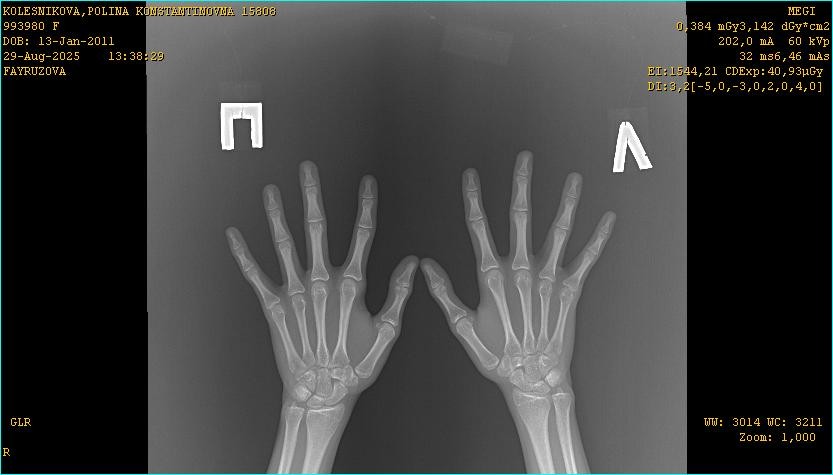

Здравствуйте, девочка 14 лет. Подскажите пожалуйста открыты ли еще зоны роста. По ренгену костный возраст на 16 лет